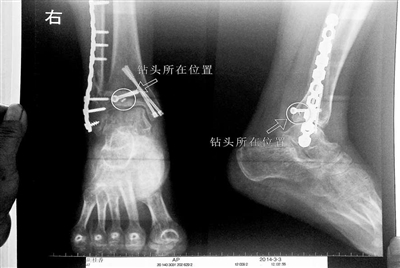

胡女士的腿部X光圖

近日,在豐臺區右安門醫院,北京青年報記者見到了胡女士,她走起路來顯得一瘸一拐,腿腳并不利索。在她帶來的X光片上,可以清晰地看到,有一個異物存在于腿內部。

“我當時就嚇蒙了,怎么會有一個鉆頭在骨頭里?”胡女士余悸未消地說,第二天拍攝的X光片顯示,2厘米左右的鉆頭遺留在她右腳腳踝上部的骨頭內。